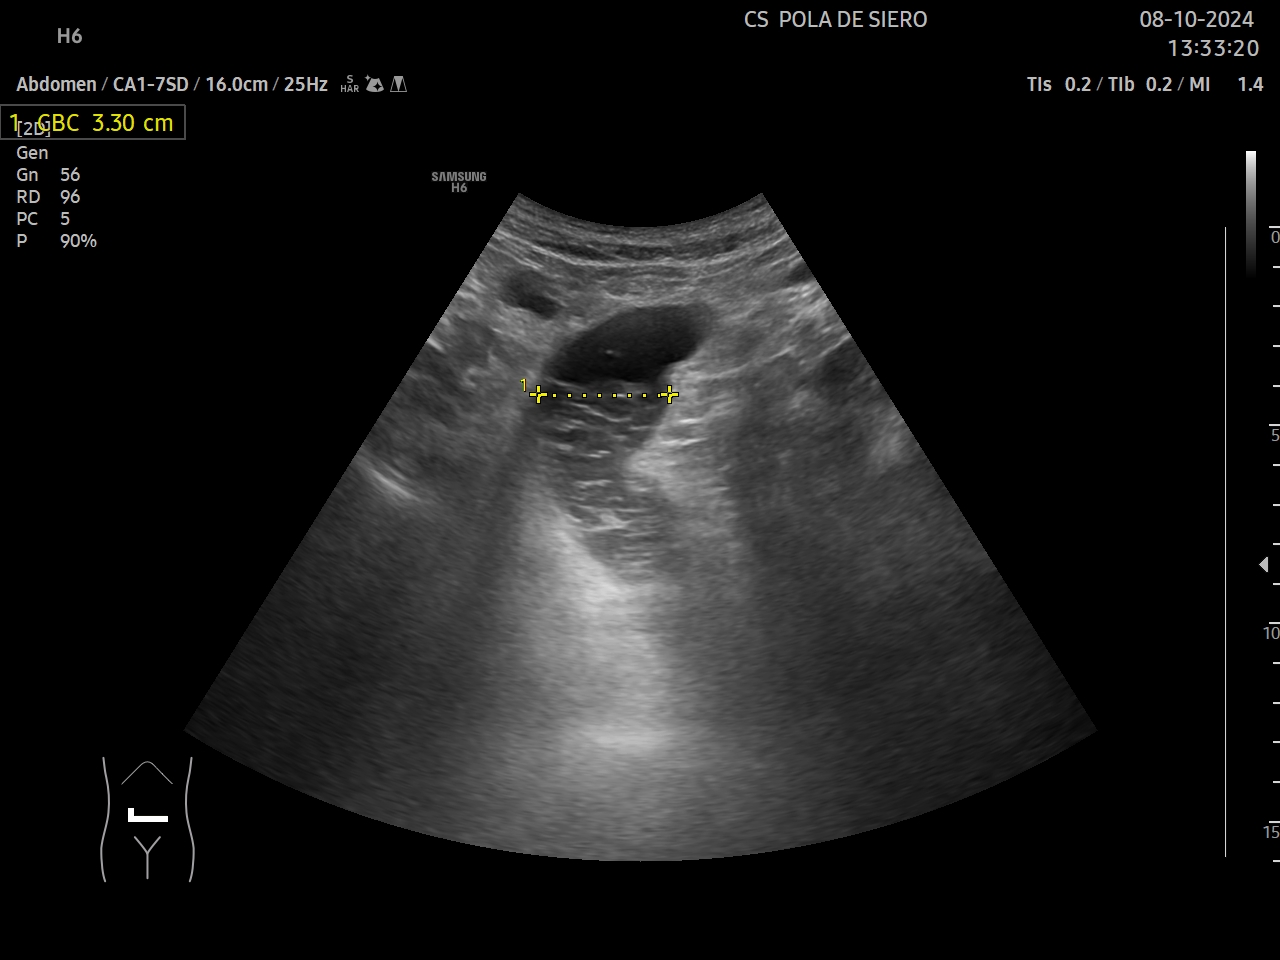

Hígado, vesícula, bazo, aorta y vejiga sin alteraciones significativas. Poliquistosis renal. No líquido libre. Se objetiva en un corte transversal en mesogastrio un asa intestinal dilatada de 3,3 cm, con muy escaso peristaltismo y objetivándose en su luz un nivel con una zona anecogénica superior y una zona hiperecogénica y heterogénea inferiormente.

Para el estudio ecográfico del tubo digestivo comenzaremos con una valoración con sonda convex del colon desde el ciego (localizado en la fosa ilíaca derecha y reconocible por su contenido con sombra acústica y falta de peristaltismo) hasta al menos el sigma proximal. Posteriormente se estudiará el intestino delgado partiendo del íleon terminal y realizando movimientos del transductor en dirección craneocaudal hasta cubrir todo el abdomen. Deben valorarse con una sonda lineal los segmentos sospechosos bien por alteraciones de la pared, del contenido intraluminal o del peristaltismo. El diámetro máximo de las asas varía entre 2 y 2,5 cm, llegado el del colon hasta los 5 cm.